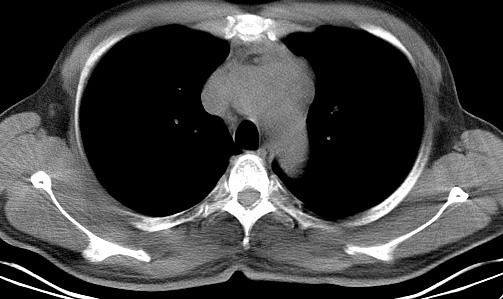

男   40   反复腹痛入院行彩超检查示胸骨右缘4、5肋间不均质回声团

淋巴瘤:前纵隔可见多组肿大的淋巴结,部分融合,有液化坏死

上区却那么有点象占位,胸腺瘤不太象,一点强化也没有,淋巴瘤气管前上腔静后却很干净,下区也点象纵隔积血征,